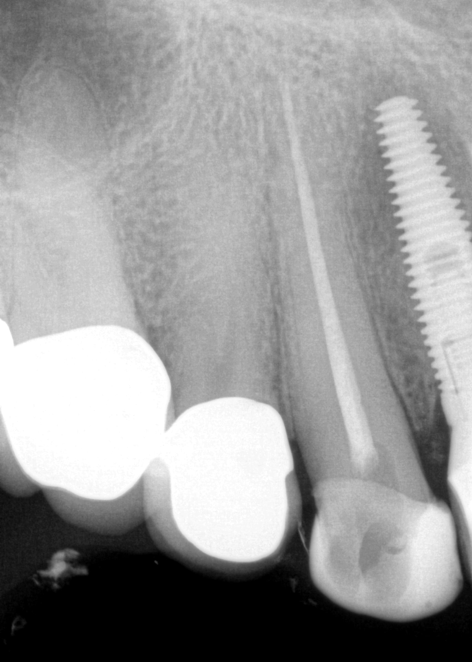

Fig 8. Gold crown removed, dentin excavated, canals shaped and filled.

Figure 8

The patient returned for final evaluation of the provisional calcium-hydroxide endodontic therapy and resolution of the infection (33 days postoperatively). Fistula was not present; the tooth was not sensitive to percussion or mastication. The gold crown was removed using a high-speed metal cutting bur, the remaining caries were excavated conservatively, and the endodontic therapy was completed. Placement of glass-fiber reinforced composite and composite core buildup took place. The natural tooth structure to receive the glass-fiber post and a long-term restoration was available (Figure 8). Within one appointment, the tooth was restored (Figure 9). The patient was instructed to return for clinical and radiographic evaluation after 6 to 12 months to determine progression of periodontal healing. At that time, if the healing were adequate and the tooth were stable, evaluation of the tooth would be considered every 3 to 4 years.7